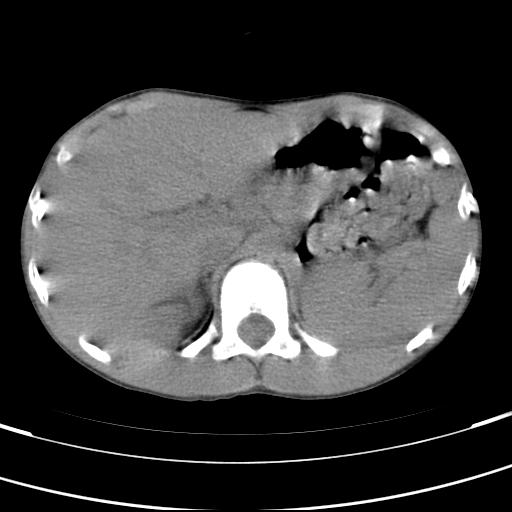

标题: PED3157:左肾缺如,请教脾脏的改变?、、

男孩,9岁。胃部不适。

脾脏位于左侧,但数个脾脏呈分离状态,左肾缺如,右肾代偿肥大。考虑多脾综合征。